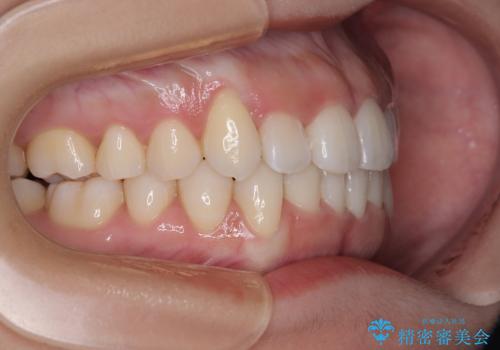

上顎の急速拡大装置を使用して上顎骨を側方に拡大することで上顎歯列を拡大し、下顎歯列も拡大できるようにすることで、歯列を整えることとしました。

歯列矯正では基本的に骨格を改善することはできませんが、急速拡大装置(MARPE)を使用することで上顎骨を側方に拡大させることができ、咬合状態を大きく改善することができます。